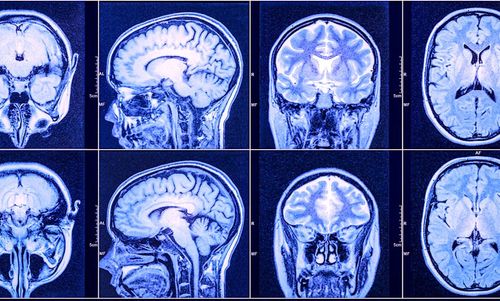

Parkinson, une terrible maladie neurologique dégénérative résultant en la perte progressive de neurones, affecte actuellement environ 160 000 français. À l'heure où de potentiels traitements curatifs sont en cours de développement, il devient d'autant plus important de diagnostiquer la maladie le plus tôt possible. Récemment, des